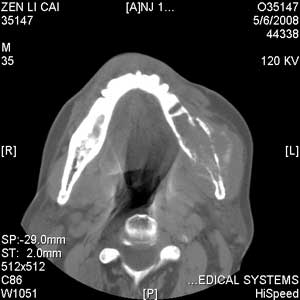

以下是引用jiangjing在2008-5-28 15:56:00的发言:[br]下颌骨左侧部骨质破坏,轻度膨胀,瘤骨形成,软组织肿胀考虑 恶性骨肿瘤-----肉瘤类